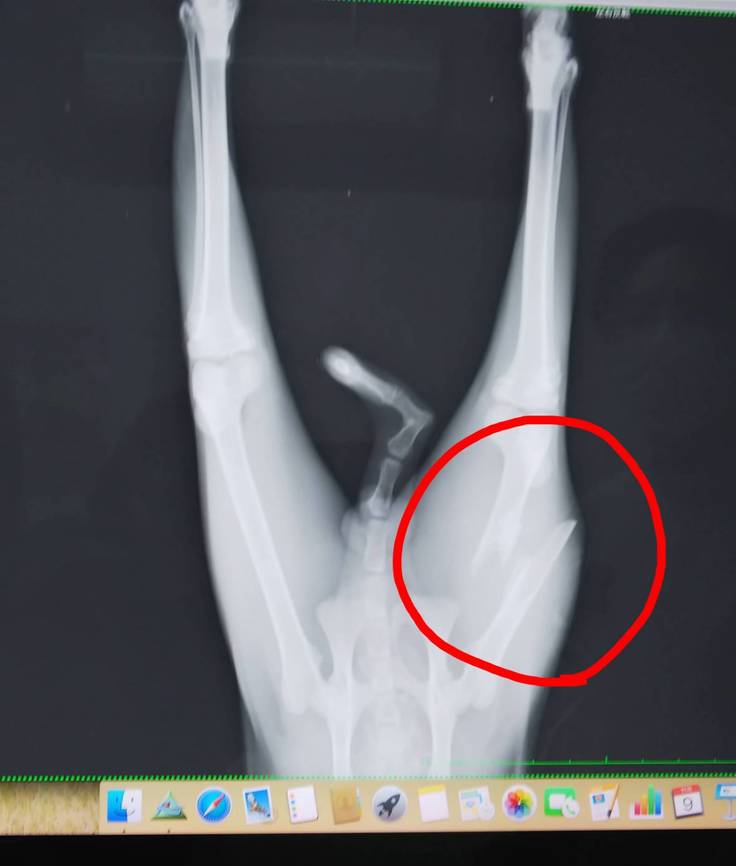

先生もすぐに、衰弱より何より足の様態が気になりますとおっしゃって、レントゲン撮影。

診断 左足大腿骨粉砕骨折

レントゲン写真を見て、愕然としました。

「おそらくバイクか何かに跳ねられたと思います。高い所からジャンプして、大腿骨折っちゃう子も、少なくないんですが、この折れ方だと、事故じゃないですかね」